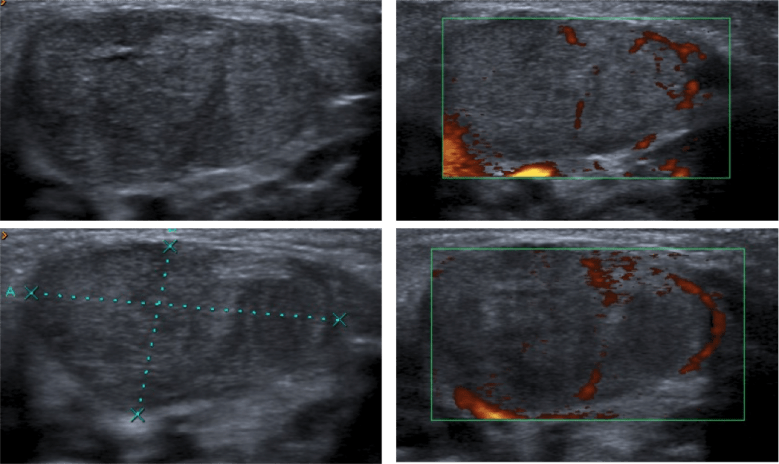

La ecografía es la técnica de elección. Siempre es la prueba inical a realizar. Se observa una masa focal o aumento de tamaño del músculo de forma difusa. Esto produce un acortamiento del mismo produce un giro de la cabeza hacia el lado contrario al afectado.

La ecogenicidad suele estar aumentada, disminuida o ser similar al músculo. La señal Doppler color puede mostrar captación de flujo con ondas de alta resistencia